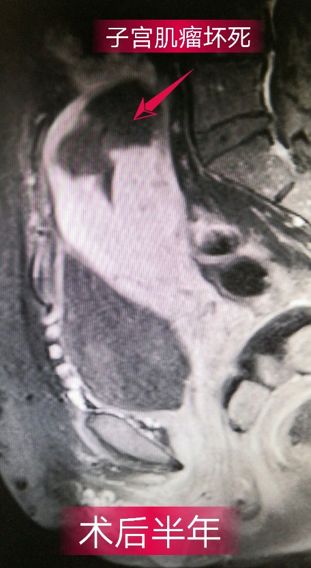

48岁,因“月经紊乱伴经量增多3年,阴道出血17天”入院,诊断为:子宫肌瘤。治疗后第一天,阴道出血停止,治疗后3个月,月经周期恢复规律,血红蛋白在正常范围,6个月复查磁共振显示子宫肌瘤已坏死、吸收、缩小。